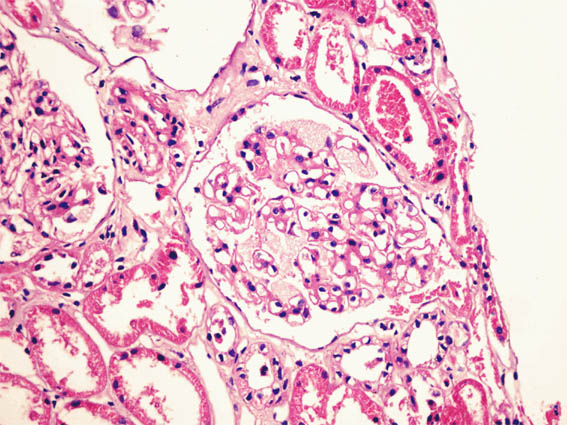

Clinical information

See the images of the renal biopsy.

Figure 2. H&E, X200.